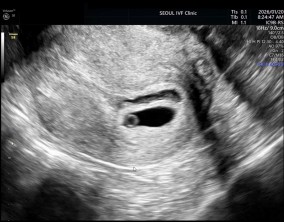

임신 수치 16, 9주차 기적의 기록

서울IVF에서는 단순히 배아 생성과 이식만 해주시는 것이 아니라, 제 생활 전반까지 신경 써주셨습니다. 휴식기에도 그저 기다리는 것이 아니라 항노화에 도움이 되는 링겔을 처방…